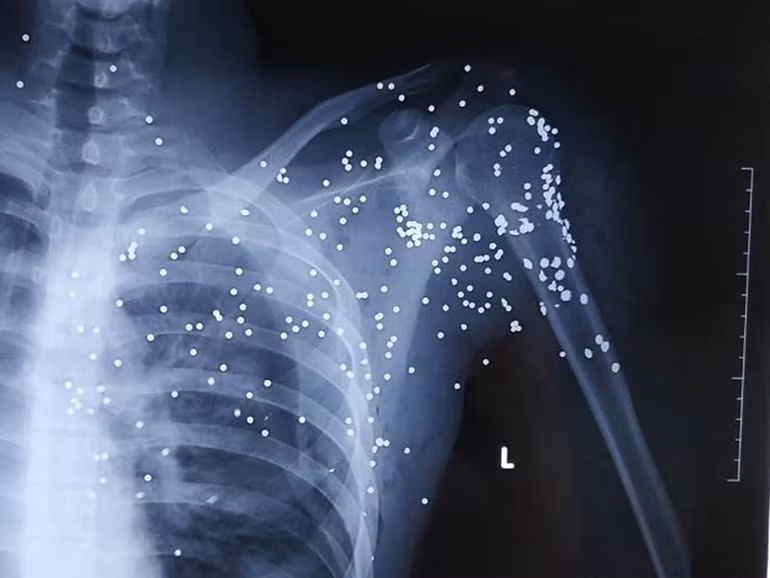

Ảnh phim chụp trên người nạn nhân Hoàng cho thấy rõ nhiều vết đạn. (Ảnh bệnh viện cung cấp)

Sau khi chụp, chiếu, xác định có nhiều vết đạn dày đặc quanh khu vực vùng phổi, bệnh viện quyết định làm thủ tục chuyển nạn nhân lên Bệnh viện Việt Đức (Hà Nội) điều trị.